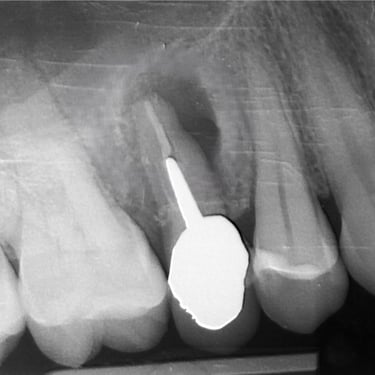

Perforación Radicular

Una perforación radicular es una abertura anormal en la raíz del diente, generalmente debido a un procedimiento dental fallido o una caries profunda.

Los pacientes pueden sentir dolor y notar hinchazón en la encía.

El tratamiento incluye la reparación de la perforación y el tratamiento de conducto. Es crucial reparar la perforación para evitar una infección.